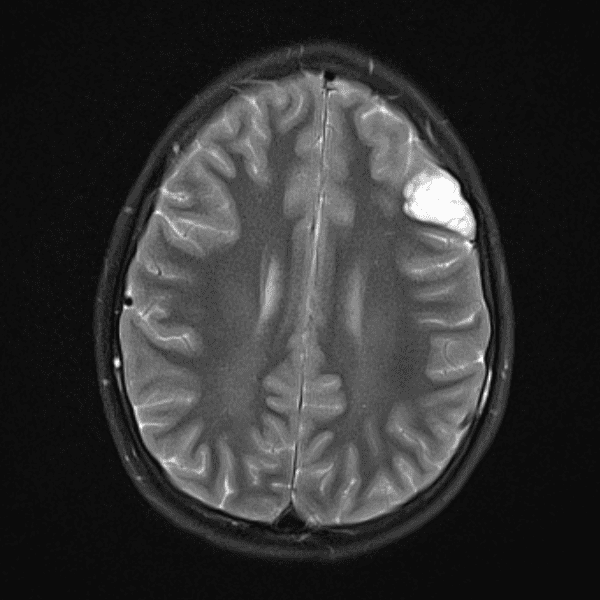

Classic Cases